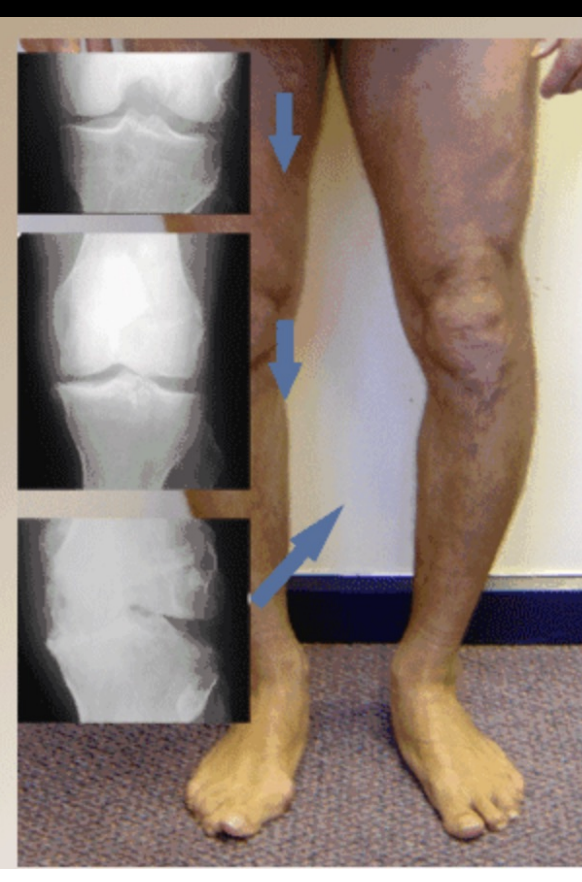

Types of Arthroplasty

unicompartmental arthroplasty

patellofemoral arthroplasty

total knee arthroplasty

Uniarthroplasty

used for isolated medial

> lateral compartment disease

all ligaments must be intact

<8% of all arthroplasties

good candidates are normal weight, elderly